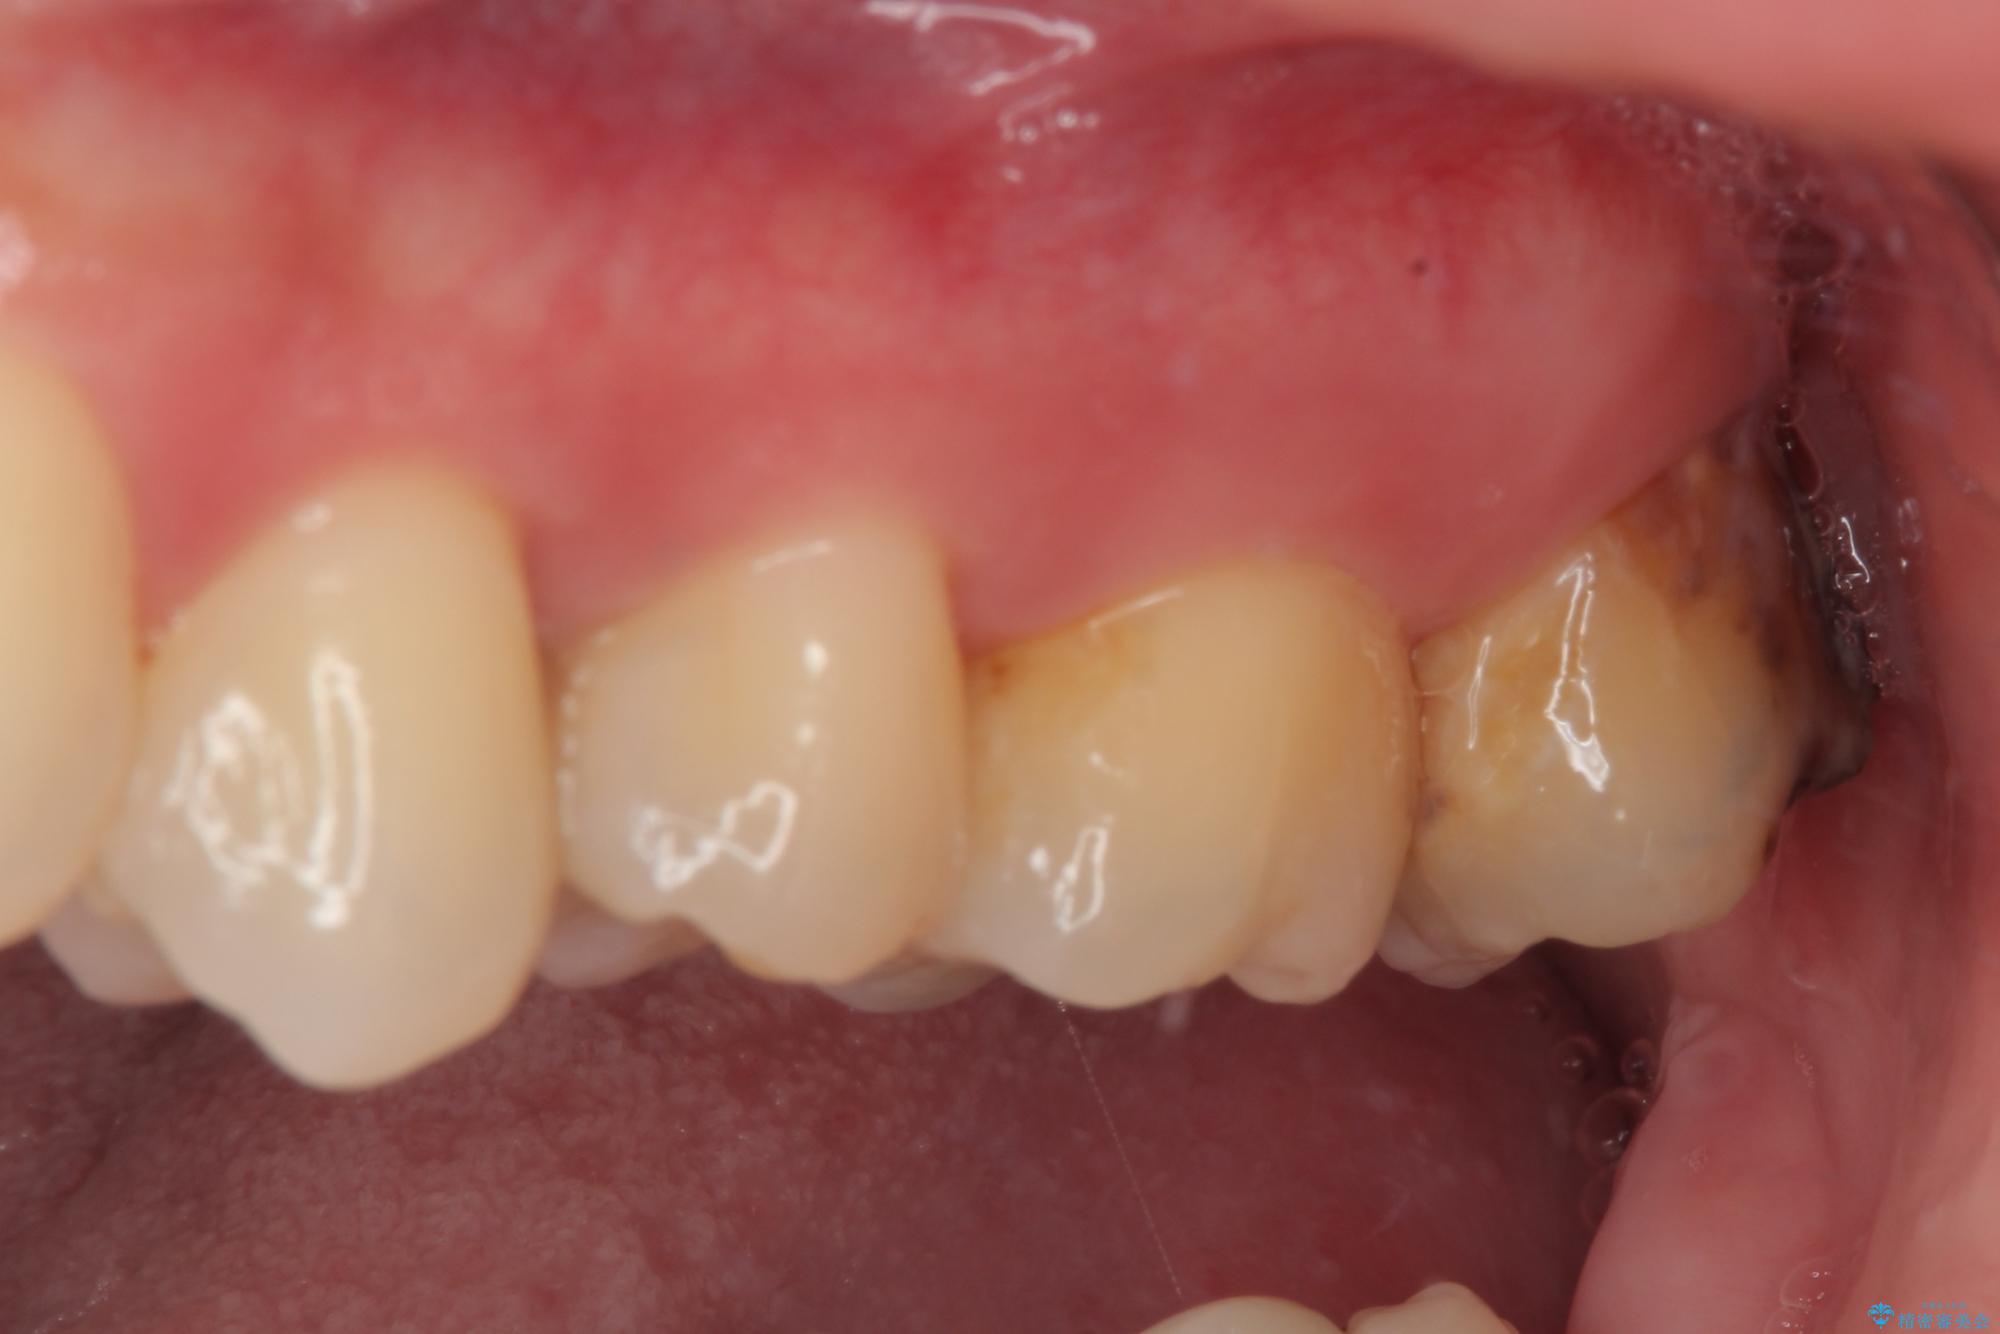

矯正治療により処置が可能な位置に歯が移動したため、オールセラミッククラウンにて補綴治療を行うこととしました。

歯列が移動したとはいえ、左右ともに後方傾斜しており、むし歯の除去、形成(形を整える)、型取りの全てが非常に困難な処置となりました。

セラミッククラウンの適合はレントゲン写真からも分かる通り、境界がぴったりと合った、高適合のものとなりました。